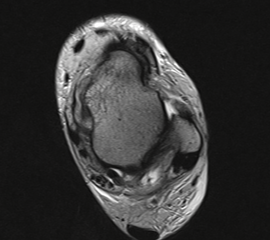

MRT

Die Kernspintomographie hat ihre Stärke in der Darstellung von Weichteilverletzungen. Insbesondere Verletzungen der Wachstumsfuge, des Periosts und der Bänder lassen sich gut visualisieren. Nachteilig ist die Untersuchungsdauer von 20-30 Minuten. Bleibt das Kind während dieser Zeit nicht ruhig liegen, kommt es zu Bewegungsartefakten, welche die Beurteilbarkeit der Bilder beeinträchtigen.